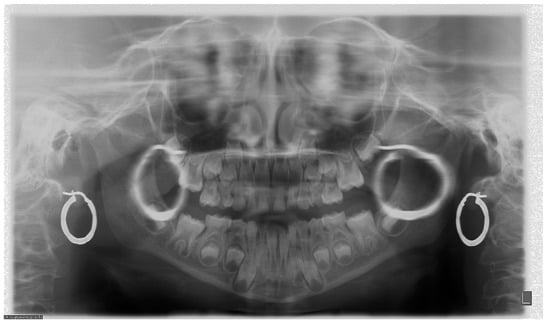

7. Metal and Motion Artefacts